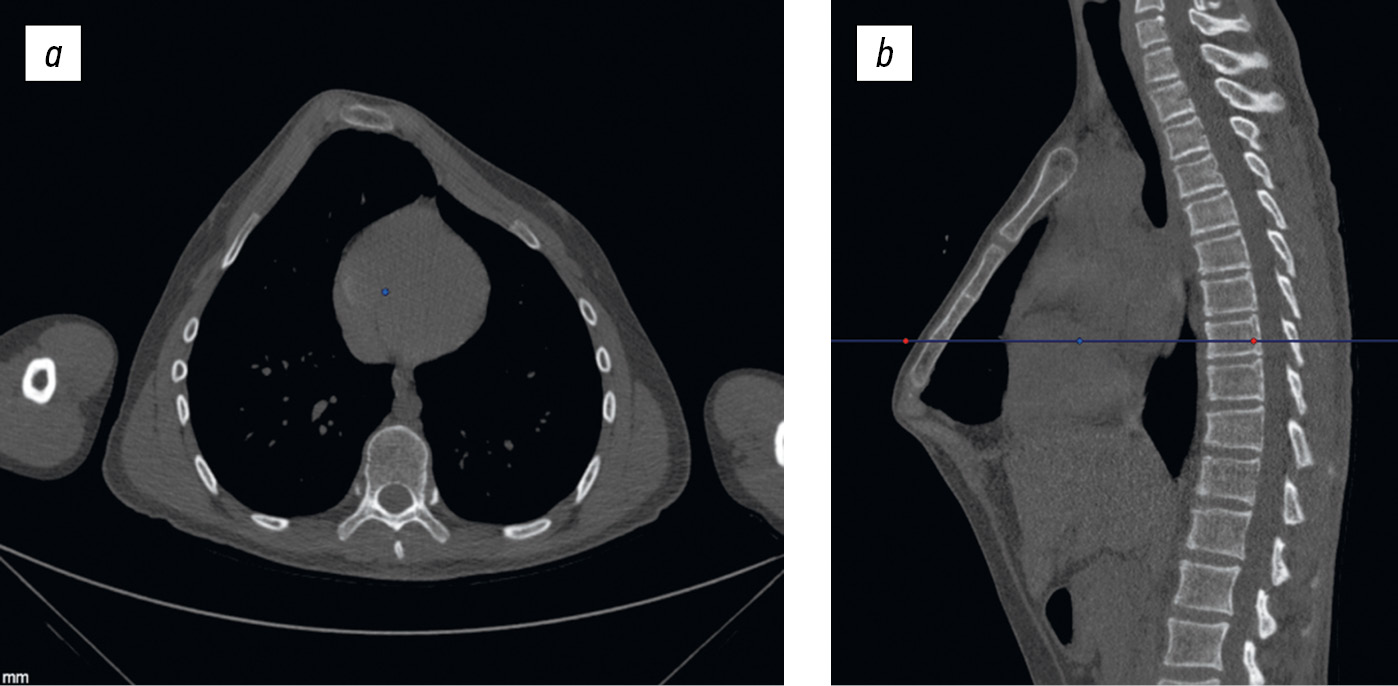

Спустя 1 год пациент был госпитализирован для удаления металлоконструкции. При этом была выполнена КТ грудной клетки и определены индексы, которые, по сравнению с ближайшим послеоперационным периодом, изменились незначительно, так же как и послеоперационный эстетический результат (рис. 5 и 6).

Рис. 5. Компьютерная томограмма грудной клетки через 1 год после оперативного лечения: горизонтальная плоскость (а, b), сагиттальная плоскость (c). Индекс Галлера 2,26, угол ротации грудины 3° — симметричная, индекс компрессии 0,8.